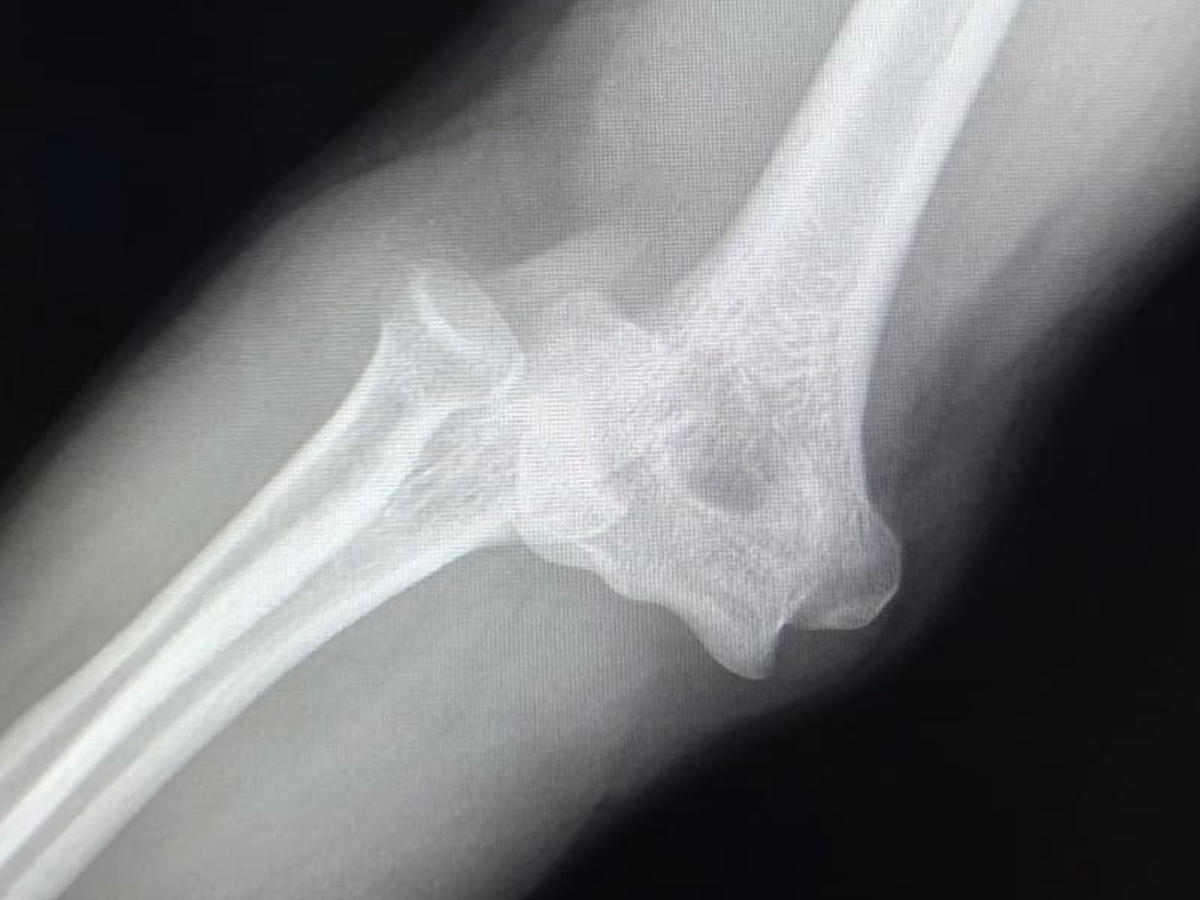

El día sábado sufrí una caída dislocándose mi codo derecho de una manera muy complicada para poder acomodarlo, tuve que viajar más de 5 hrs para poder encontrar atención médica capacitada para que realizaran la reducción (acomodo del hueso) pero al hacerlo se produjeron 2 fracturas, hasta hoy la cuenta médica asciende a $190,000 y sumando, ayúdenme a salir de esto.